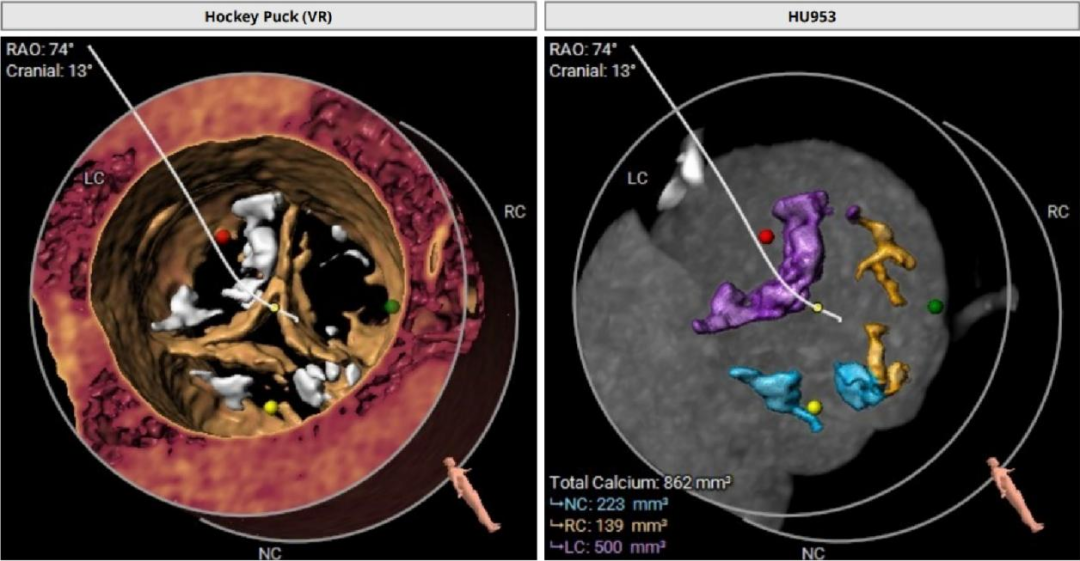

瓣叶重度钙化合并增厚,钙化分布不均,主要集中于左冠窦内。

HU953 积分862mm²。